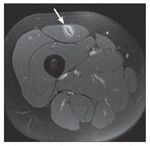

Injuries of the rectus femoris central tendon contributed to a significantly longer rehabilitation interval than injuries located in the periphery of the rectus femoris and the vastus muscles. Fluid enhancement around the central tendon, the so-called acute bull's-eye lesion (Figure 3), also revealed a significantly worse prognosis (rehabilitation interval, 26.8 days vs 9.2 days) compared with lesions found around the periphery of the rectus femoris.24

Figure 3 –

An axial MRI view of a rectus femoris central tendon injury shows fluid enhancement around the central tendon, the acute bull’s-eye lesion (arrow). The injury has a significantly worse prognosis than lesions found around the periphery of the rectus femoris.